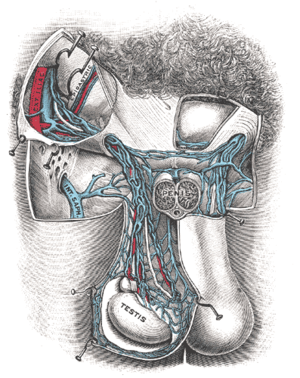

| مقطع عرضي يوضح الإصابة بدوالي الخصية. | |

دوالي الخصية Varicocele، هي عن ضعف خلقي في جدار الأوردة الدموية الموجودة بالخصية، ما يؤدي إلى سخونتها وارتفاع درجة الحرارة بالخصيتين، فتقل كمية الأكسجين المتجهة [[حيوانات منوية|للحيوانات المنوية] والضرورية لحيويتها، كما أن تلك الأوردة هي التي تحمل الدم (الفاسد) الراجع من الخصية، وهي في هذا شبيهة بما يحدث في دوالي الساقين، حيث تعجز الصمامات المتواجدة داخل هذه الأوردة عن مهمتها في الحفاظ على سريان الدم في اتجاه واحد من أسفل إلى أعلى، فتتوسع هذه الأوردة مع زيادة قطرها وطولها وتلتوي على شكل حلزوني.

تصيب دوالي الخصية 15% من الرجال، وهي أكثر شيوعا في الناحية اليسرى، وقد يكون لها تأثير على القدرة الإنجابية للرجل؛ فانخفاض عدد الحيوانات المنوية وتدني النسبة المئوية لحيويتها في حالة وجود دوالي الخصية هو دليل كافٍ على أن الدوالي هي السبب الأساسي لهذه العلة والتي تشكل 40% من حالات عدم الإنجاب لدى الرجال.